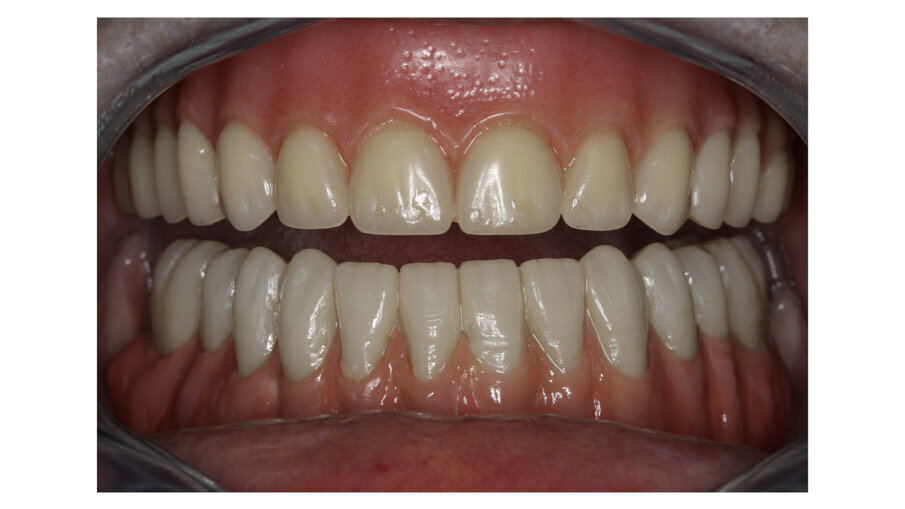

Another common situation is a full mouth restoration over implant. It is well known that the big issue is chipping and delimitation of the ceramics, due to the high forces applied in the patient with dental implants. In regards to this problem, the combination of rigid materials to support the connectors and resilient materials to absorb the shock and, at the same time, allow easy fixation, make the use of resin based blocks the logical choice for this kind of restoration (Figs. 6-8).

Fig. 8: Upper and lower bridges in the mouth.